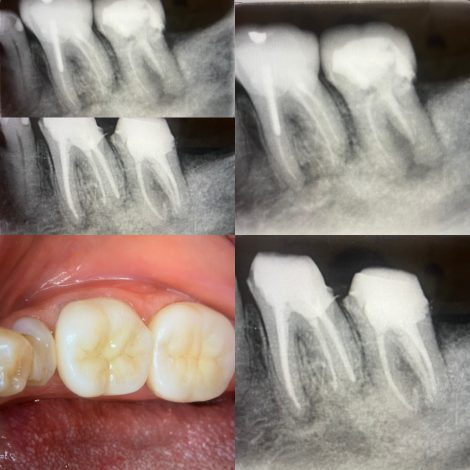

本日ご紹介する症例🦷

難易度の高い大臼歯の根管治療

おそらく前医の先生も苦労した様子